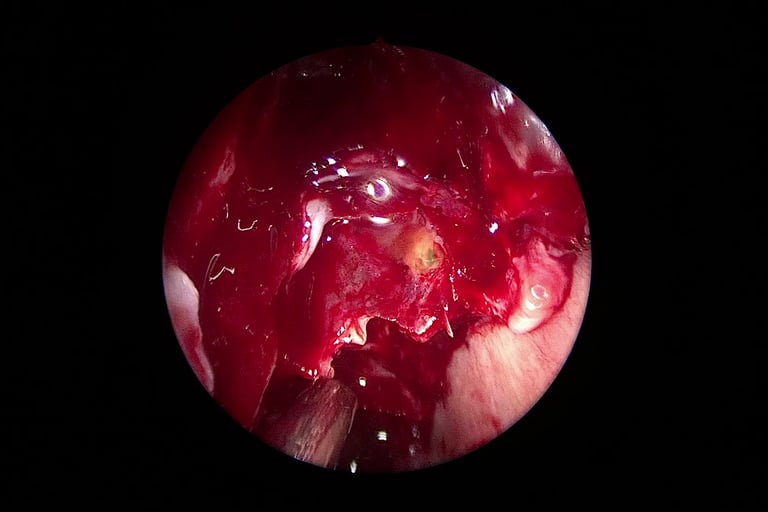

U odabranim slučajevima koristi se i intratekalni fluorescein, koji se ubrizgava u likvorski prostor – istjecanje se tada vidi pod plavim svjetlom, što olakšava pronalaženje mjesta defekta tijekom operacije

Danas je zlatni standard za većinu slučajeva likvoreje upravo endoskopska kirurgija nosa i baze lubanje. Ova tehnika omogućuje:

Precizno zatvaranje defekta kroz nosnice

Korištenje vlastitih tkiva (npr. septalna sluznica, masno tkivo, fascija) ili bioloških materijala za zatvaranje